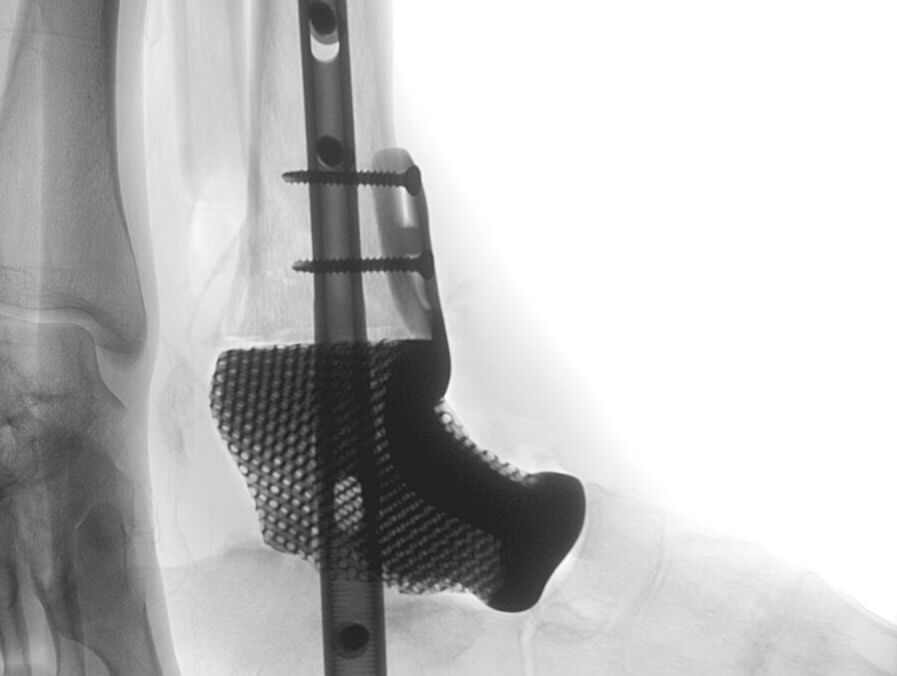

בשלב זה התקבלה החלטה אמיצה וחדשנית: הוצאת העצם הפגועה ושימוש בחומר ייעודי לשימור הקרסול. לאחר מספר חודשים, כשהבדיקות היו תקינות ובדיקת ה-CT אישרה את המצב, ניתן היה לצאת לדרך. עבור המטופל הודפס משתל מותאם אישית מטיטניום, שנועד לגשר על חסר עצם משמעותי ולשמר את אחד משלושת המפרקים בקרסול. המשתל בנוי כך שחלקו מסולסל ומעודד צמיחת עצם לתוכו, וחלקו החלק מותאם למפרק שנשמר.

עד היום, במצבים רפואיים דומים, היה נהוג להקריב את שלושת המפרקים, הליך שמוביל לנטרול מוחלט של התנועה. בניתוח הנוכחי הצליחו באיכילוב, לראשונה בישראל, לשמר חלק מהתנועתיות בקרסול באמצעות המשתל החדש והמדויק.